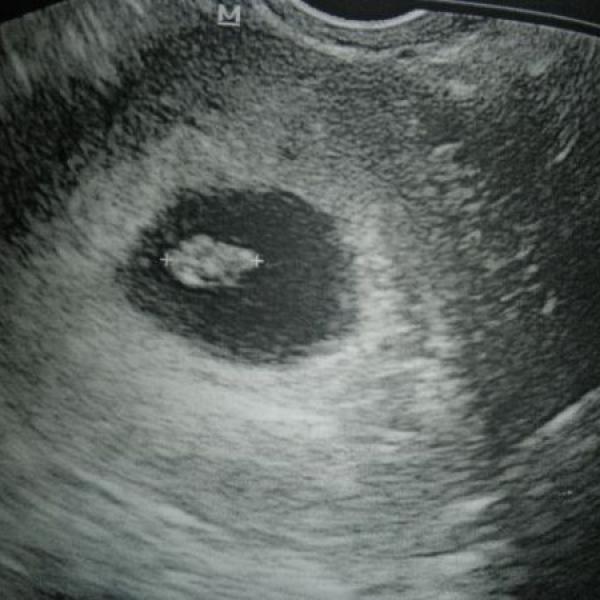

Ahoj holky, tak jsem dnes byla na prvním ultrazvuku a je to tam :-))) Všechno zatim vypadalo dobře, srdíčko bouchalo krásně, i jsem ho slyšela, to bylo radosti :-) Dle MS jsem 7+0 a dle UZ 6+6